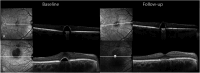

Methods: In this retrospective study, 54 eyes of 48 patients with pachychoroid-related disease were treated with prednisolone acetate 1% eye drops 3 times a day. Change in macular volume and retinal central subfield thickness on optical coherence tomography was measured. In addition, the foveal or complete resolution of fluid and the change in visual acuity were studied.

Results: The follow-up visit was at a mean of 41.2 ± 14.5 days. In the 44 eyes with chronic central serous chorioretinopathy, a significant reduction in retinal central subfield thickness ( P < 0.001) and macular volume ( P < 0.001) was observed. Foveal intra- or subretinal fluid resolved completely in 22% of the eyes. In the 8 peripapillary pachychoroid syndrome eyes, a reduction in the nasal retinal thickness was observed ( P = 0.025). One of the 2 pachychoroid pigment epitheliopathy eyes showed structural improvement. No significant change in visual acuity was observed in any of the pachychoroid spectrum diseases.